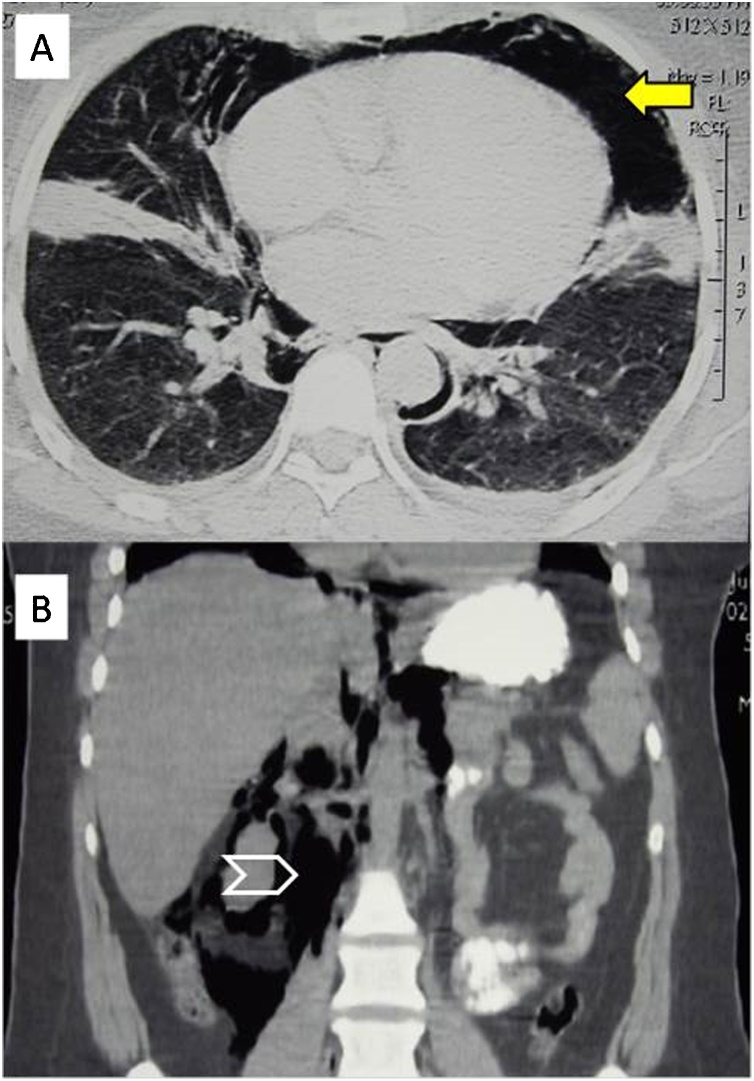

All patients had abdominal pain and tenderness. Table 2 shows a comparison between the early (within 12 h) and late (12−24 h) clinical findings of the same patients. Perforation was discovered during the ERCP in one patient (16.6 %). In the remaining five, the median (range) time to diagnosis was 13.5 (3.5–24) hours. Following the persistence of abdominal findings, five patients (83.33 %) underwent abdominal CT Scan with oral contrast as the main diagnostic method (Fig. 2). Retroperitoneal air was detected in all five patients, two of whom were found to have surgical emphysema, and both underwent surgery. Two patients had pneumothorax on the right side.

Retroperitoneal air (RPA) is present in all types of post-ERCP perforations. Nevertheless, it is not an absolute indication for surgery [ref. 4]. In our study RPA was found in all five patients who had CT scan, two of them were managed non-surgically. The amount of RPA does not indicate the size or the seriousness of perforation; it is likely related to the amount of air insufflated in a protracted procedure [ref. 4,ref. 11]. Surgical emphysema can be an alarming sign for the need for early surgery. In our study, the two patients who had surgical emphysema needed surgery. The leaking air through the crura of the diaphragm may cause tension pneumothorax that must be suspected when there is unexplained chest pain, hypotension and dyspnea following an ERCP [ref. 13].